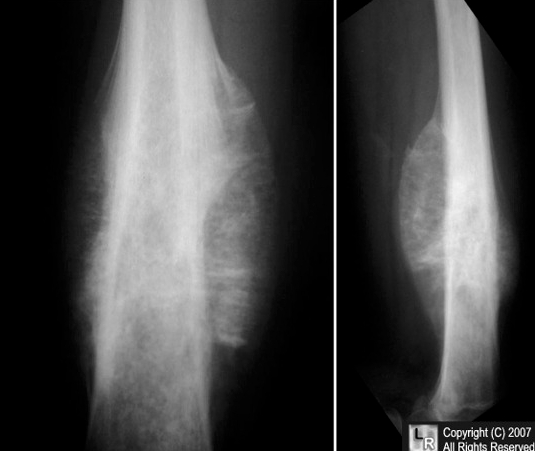

X-ray imaging in Ewing sarcoma shows a destructive lesion in the diaphysis and/or metaphysis of long bones with a classic “moth-eaten appearance.” A periosteal reaction in Ewing sarcoma may show periosteal elevation or “onion-skin” lesions on x-ray imaging.